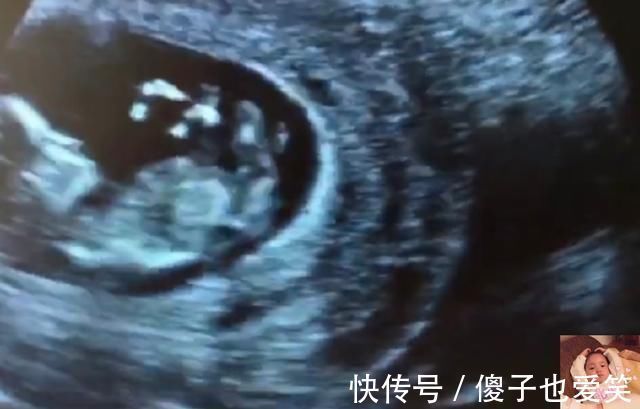

4)打个哈欠

11周后胎宝宝,已经学会了打哈欠,吃完饭后,胎宝宝有些困了,打个哈欠表示自己要睡觉了哦。